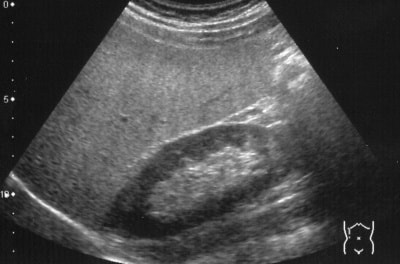

腹部超音波検査

超音波検査では、腫瘍などの有無だけでなく、その大きさや深達度(どのくらいの深さまで達しているか)も調べることができます。また、映し出される画像は、臓器がリアルタイムで動いて見えます。そのため、検査のための組織を採取したり、臓器の位置を確認しながら治療を行うときに使われることもあります。

さらに、この検査はX線検査のように放射線被爆の心配がなく、検査を受ける人の苦痛もなく安全です。